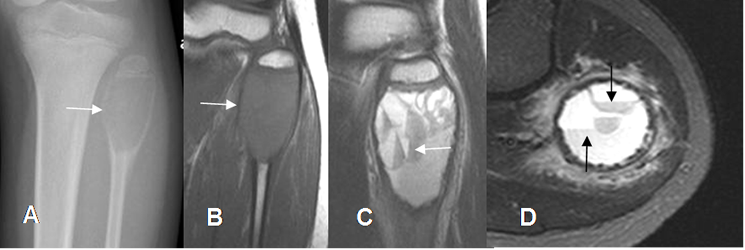

Fig 142. Quiste óseo aneurismático.

A: Rx AP y B: RM coronal en T1. Lesión expansiva, radiolúcida y de comportamiento benigno, en la metafisis de la cabeza del peroné en un adolescente.

C: RM sagital en T2 y D: RM axial en STIR. Se identifican niveles líquido/líquido, por quiste óseo aneurismático.